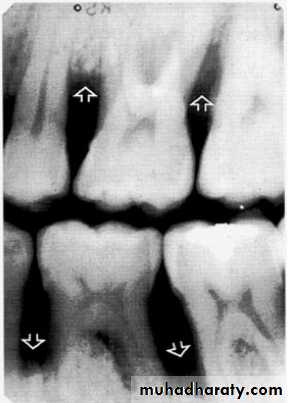

Direction :

Intercrestal bone should be parallel with line dawn from the CEJ of one tooth to that of the contacting tooth.

1. Horizontal bone loss:- When loss occurs on a plane that is parallel with a line drown.

Detection of Periodontal Disease

2.Vertical bone loss:- when there is greater bone loss in one tooth than on the adjacent tooth, so the bone level is not parallel with a line joining the CEJ.